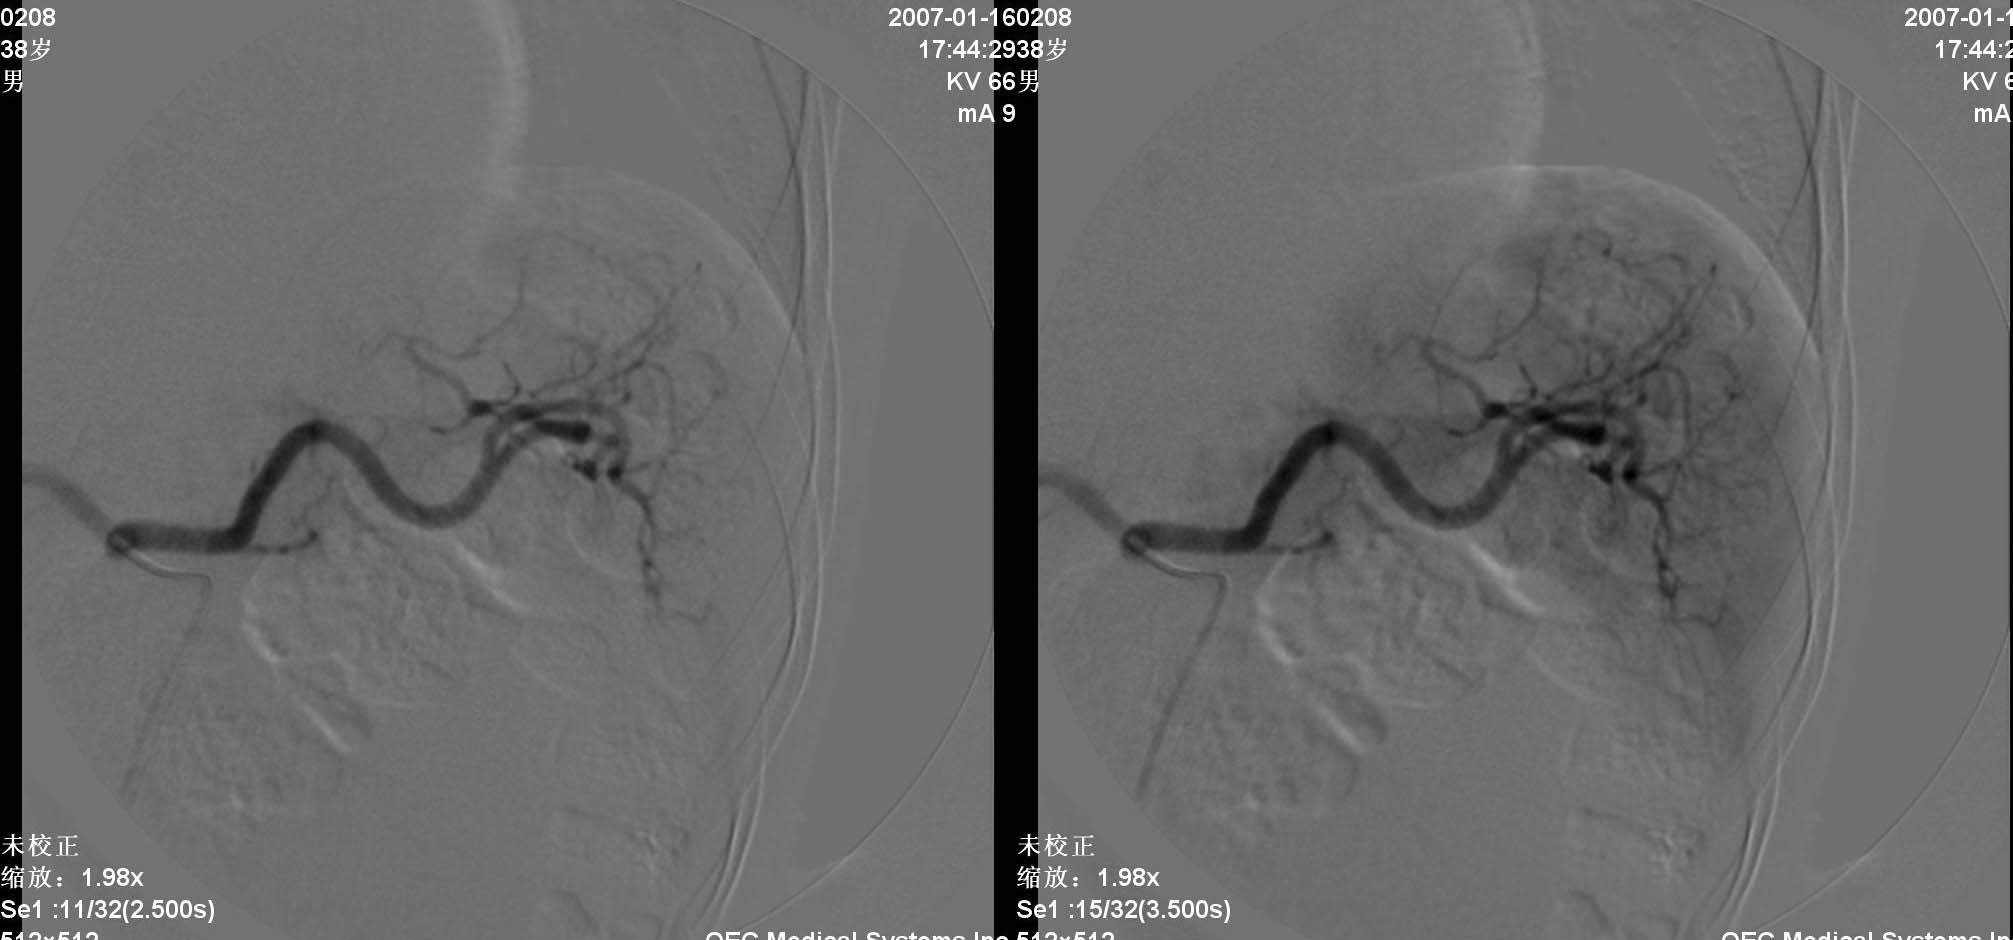

患者男性,38岁,因血便4天入院.查体:神请,颈无抵抗,心肺听诊无异常.腹部平软,肝肋下两指,轻度扣击痛,肠鸣音正常,神经系统无阳性发现.2006年6月份因结肠癌行右半结肠切除术.入院化验阳性结果:癌胚抗原增高.b超发现右肝两处异常,ct显示右肝及脾脏均为多个低密度病灶,肠镜显示降结肠息肉.

动脉期见肝右动脉稍增粗,实质期肝右叶可见两个类圆形染色区,以边缘部为著.脾脏病灶类似.首先考虑转移瘤.

诊断:1)肝转移瘤;2)肝血管瘤。

肝转移瘤的表现多种多样,血供丰富的肝转移瘤常呈现与肝细胞癌相似的表现,肝动脉增粗、扭曲,分支血管增多、紊乱呈网状,血管僵硬、受压移位等.巨块型转移灶实质期肿瘤染色还可见到较明显的中心性坏死所显示的中央低密度区。少血供者,肿瘤血管常较稀少、纤细、僵直或包绕,实质期肿瘤染色淡薄或不显影,而在肝实质染色衬托下形成低密度充盈缺损区。中血供之表现介于上述两者之间。在门静脉期,无论是多、中、少血供肝转移瘤,均显示与转移灶在动脉晚期和实质期类似的肿瘤染色。

肝转移瘤与原发性肝癌的血管造影表现在有些方面相似。在原发性肝癌中,动静脉瘘及门静脉癌栓的发生率是比较高的。肝转移瘤中少血供者占大部分,血管表现为纤细、稀少、僵硬,肿瘤染色较浅;而在原发性肝癌中,血管表现多为增粗、扩张、扭曲,分支血管增多、紊乱等。

肝内多发肿块是肝转移瘤的特征,而原发性肝癌一般常为单发或仅出现少量病灶。右叶多发少血供占位病变可首先考虑转移瘤。

五、血管瘤

血管瘤的dsa诊断与ct诊断同一理论,但通常出现“枝头挂果征”象或“腊梅征象”,征象出现一般见于较大血管瘤,较大血管瘤也可出现动静脉短路(avs),此例血管瘤较小,“枝头挂果征”不明显。